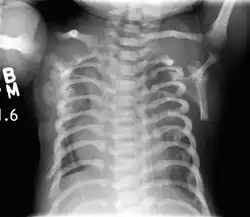

CXR of a newborn with asphyxiating thoracic dysplasia. Note the short ribs.

Lateral CXR of the same person above

Jeune syndrome is a rare genetic disorder that affects the way a child's cartilage and bones develop. It begins before the child is born and primarily affects the child's rib cage, pelvis, arms and legs.[5] Usually, problems with the rib cage cause the most serious health problems for children with Jeune syndrome. Their rib cages (thorax) are smaller and narrower than usual, which inhibits the child's lungs from developing fully or expanding when they inhale. The child may breathe rapidly and shallowly. They may have trouble breathing when they have an upper or lower respiratory infection, like pneumonia. Breathing trouble can range from mild to severe. In some children, it is not noticeable, aside from fast breathing; however, in others, breathing problems can be fatal. About 60% to 70% of children with this condition die from respiratory failure as babies or young children. Children with Jeune syndrome who survive often develop problems with their kidneys, and over time they may experience kidney failure.[2] As a result, few children with Jeune syndrome live into their teen years. Children with Jeune syndrome have a form of dwarfism. They are short in stature, and their arms and legs are shorter than most people's.[6]